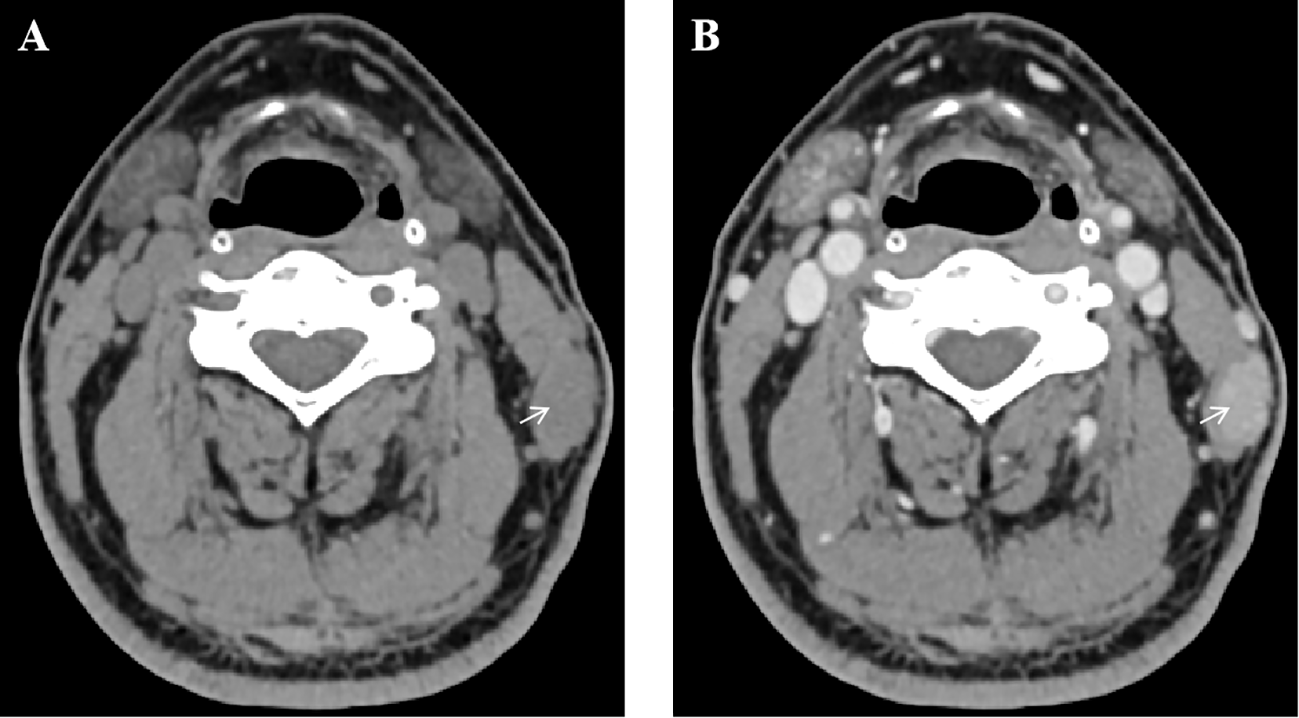

Primary non-Hodgkin lymphoma (NHL) arising in skeletal muscle is exceedingly rare. We present a case of low-grade B-cell NHL involving the sternocleidomastoid muscle . A 67-year-old male presented with an asymptomatic, slowly growing left neck mass. Imaging revealed a 17 mm × 11 mm intramuscular nodule, initially suggestive of a benign lesion. Excisional biopsy demonstrated lymphoid proliferation with muscle infiltration. Immunohistochemistry revealed CD20(+), PAX5(+), BCL2(+), and monoclonal IgH rearrangement, consistent with low-grade B-cell NHL, most likely extranodal marginal zone lymphoma (ENMZL), non-gastric/non-cutaneous type. Staging confirmed Lugano stage I disease. Given the indolent nature, the patient was managed with active surveillance. This case highlights an unusual intramuscular presentation of NHL, emphasizing the importance of histopathological and molecular evaluation for accurate diagnosis and tailored management.